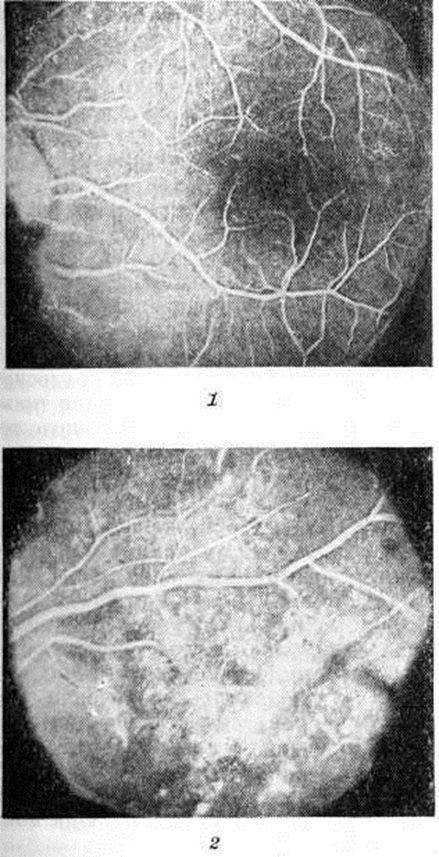

Рис. 2.

Микропрепарат ткани головного мозга (сахарный диабет): нарушение мозгового кровообращения; стенки мелких сосудов-капилляров, артериолы имеют гомогенный вид (указаны стрелками). Окраска по Ван-Гизону; × 200.

Рис. 3.

Электронограмма и микропрепарат микроциркуляторного русла кожи больного сахарным диабетом (биопсия): на электронограмме выражено утолщение и уплотнение базальной мембраны (1) капилляра кожи и набухание митохондрий (2) × 25 000. Вверху справа — микропрепарат склерозированной артериолы кожи: видны пролиферированные вакуолизированные эндотелиальные клетки (окраска гематоксилинэозином; × 200).

Поражение капилляров и венул состоит в утолщении их базальных мембран, повреждении, пролиферации эндотелия и перицитов и отложении в сосудах гликопротеидных веществ. Микроангиопатия особенно часто развивается в почках, сетчатке глаза (рисунок 1), коже (рисунок 3), мышцах и периневральных пространствах. Иногда она возникает раньше клин, проявлений Диабет сахарный и постепенно прогрессирует. При этом степень выраженности изменений микроциркуляторного русла определяется не столько длительностью Диабет сахарный, сколько степенью его компенсации при лечении. Повреждение, неравномерное утолщение базальных мембран, мукоидное набухание основного вещества сопровождаются нарушением сосудистой проницаемости. В эндотелии выявляется активный пиноцитоз (смотри полный свод знаний), альтерация и десквамация клеток. Реактивные изменения состоят в пролиферации эндотелия и перицитов, накоплении тучных клеток в периваскулярных пространствах. Синтез вещества базальных мембран эндотелием и перицитами, активация синтеза тропоколлагена приводят к необратимым изменениям в виде гиалиноза и склероза сосудов (рисунок 2).